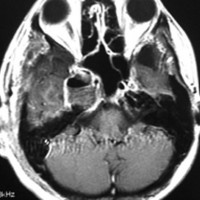

何も治療をしなくてもいい高齢者の三叉神経鞘腫,自然に小さくなります

これもメッケル腔(ガッセル神経節)という場所から発生した三叉神経鞘腫です。70代後半の女性に見つかったものです。左が2001年,右が2006年です。顔面の軽いしびれだけが症状で13年くらい経過観察していますが,大きくならないし,腫瘍の内部が壊死になってきています。何の治療もする必要のないものです。高齢者の三叉神経鞘腫は自然に小さくなること(自然退縮)があります。